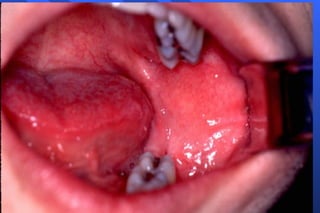

Inferior Alveolar Nerve Block Technique Apply topical Area of insertion : medial ramus, mid-coronoid notch, level with occlusal plane (1 cm above), 3/4 posterior from coronoid notch to pterygomandibular raphe advance to bone (20-25 mm)

Inferior Alveolar Nerve Block  Target Area Inferior alveolar nerve, near mandibular foramen Landmarks Coronoid notch Pterygomandibular raphe Occlusal plane of mandibular posteriors

Inferior Alveolar NerveBlock Target Area Inferior alveolar nerve, near mandibular foramen Landmarks Coronoid notch Pterygomandibular raphe Occlusal plane of mandibular posteriors

Inferior Alveolar NerveBlock Technique Apply topical Area of insertion : medial ramus, mid-coronoid notch, level with occlusal plane (1 cm above), 3/4 posterior from coronoid notch to pterygomandibular raphe advance to bone (20-25 mm)